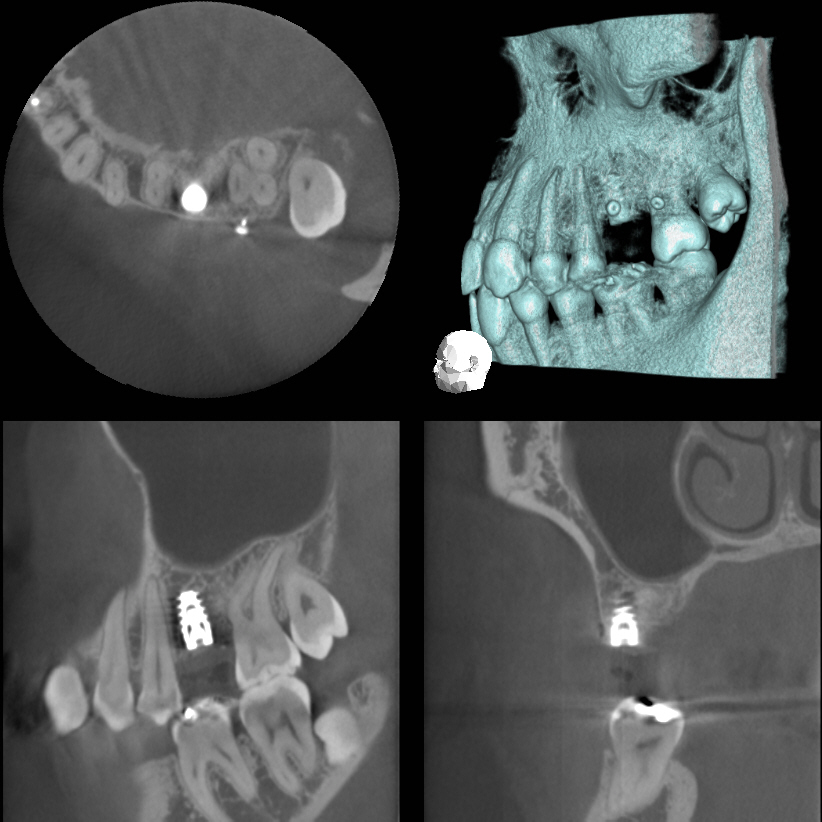

まず、かみあわせの精査のためのキャディアックスとセファロ分析をさせていただき歯周病改善のための予防プログラムにはいり、左右の下の奥歯にはインプラントを2本づつ埋入させていただきました。すべての歯にプロビショナルレスト(治療用の仮の歯)を装着させていただき。咬み合わせの安定歯肉の腫れ出血がない状態をしみや痛みがない状態を確認した後に、すべてプロセラで歯を作らせていただきました。

プロセラを使わせていただいたため、歯の切削量を少なくすることができ、結果としてほとんど神経を残してかぶせることができました。また歯に生じたヒビや穴は奥歯の不足による負担過重と歯ぎしりによるものでしたからこのような歯は内部の神経が自然に細くなっておりこのことがまた神経を残してもしみない要件の一つでした。